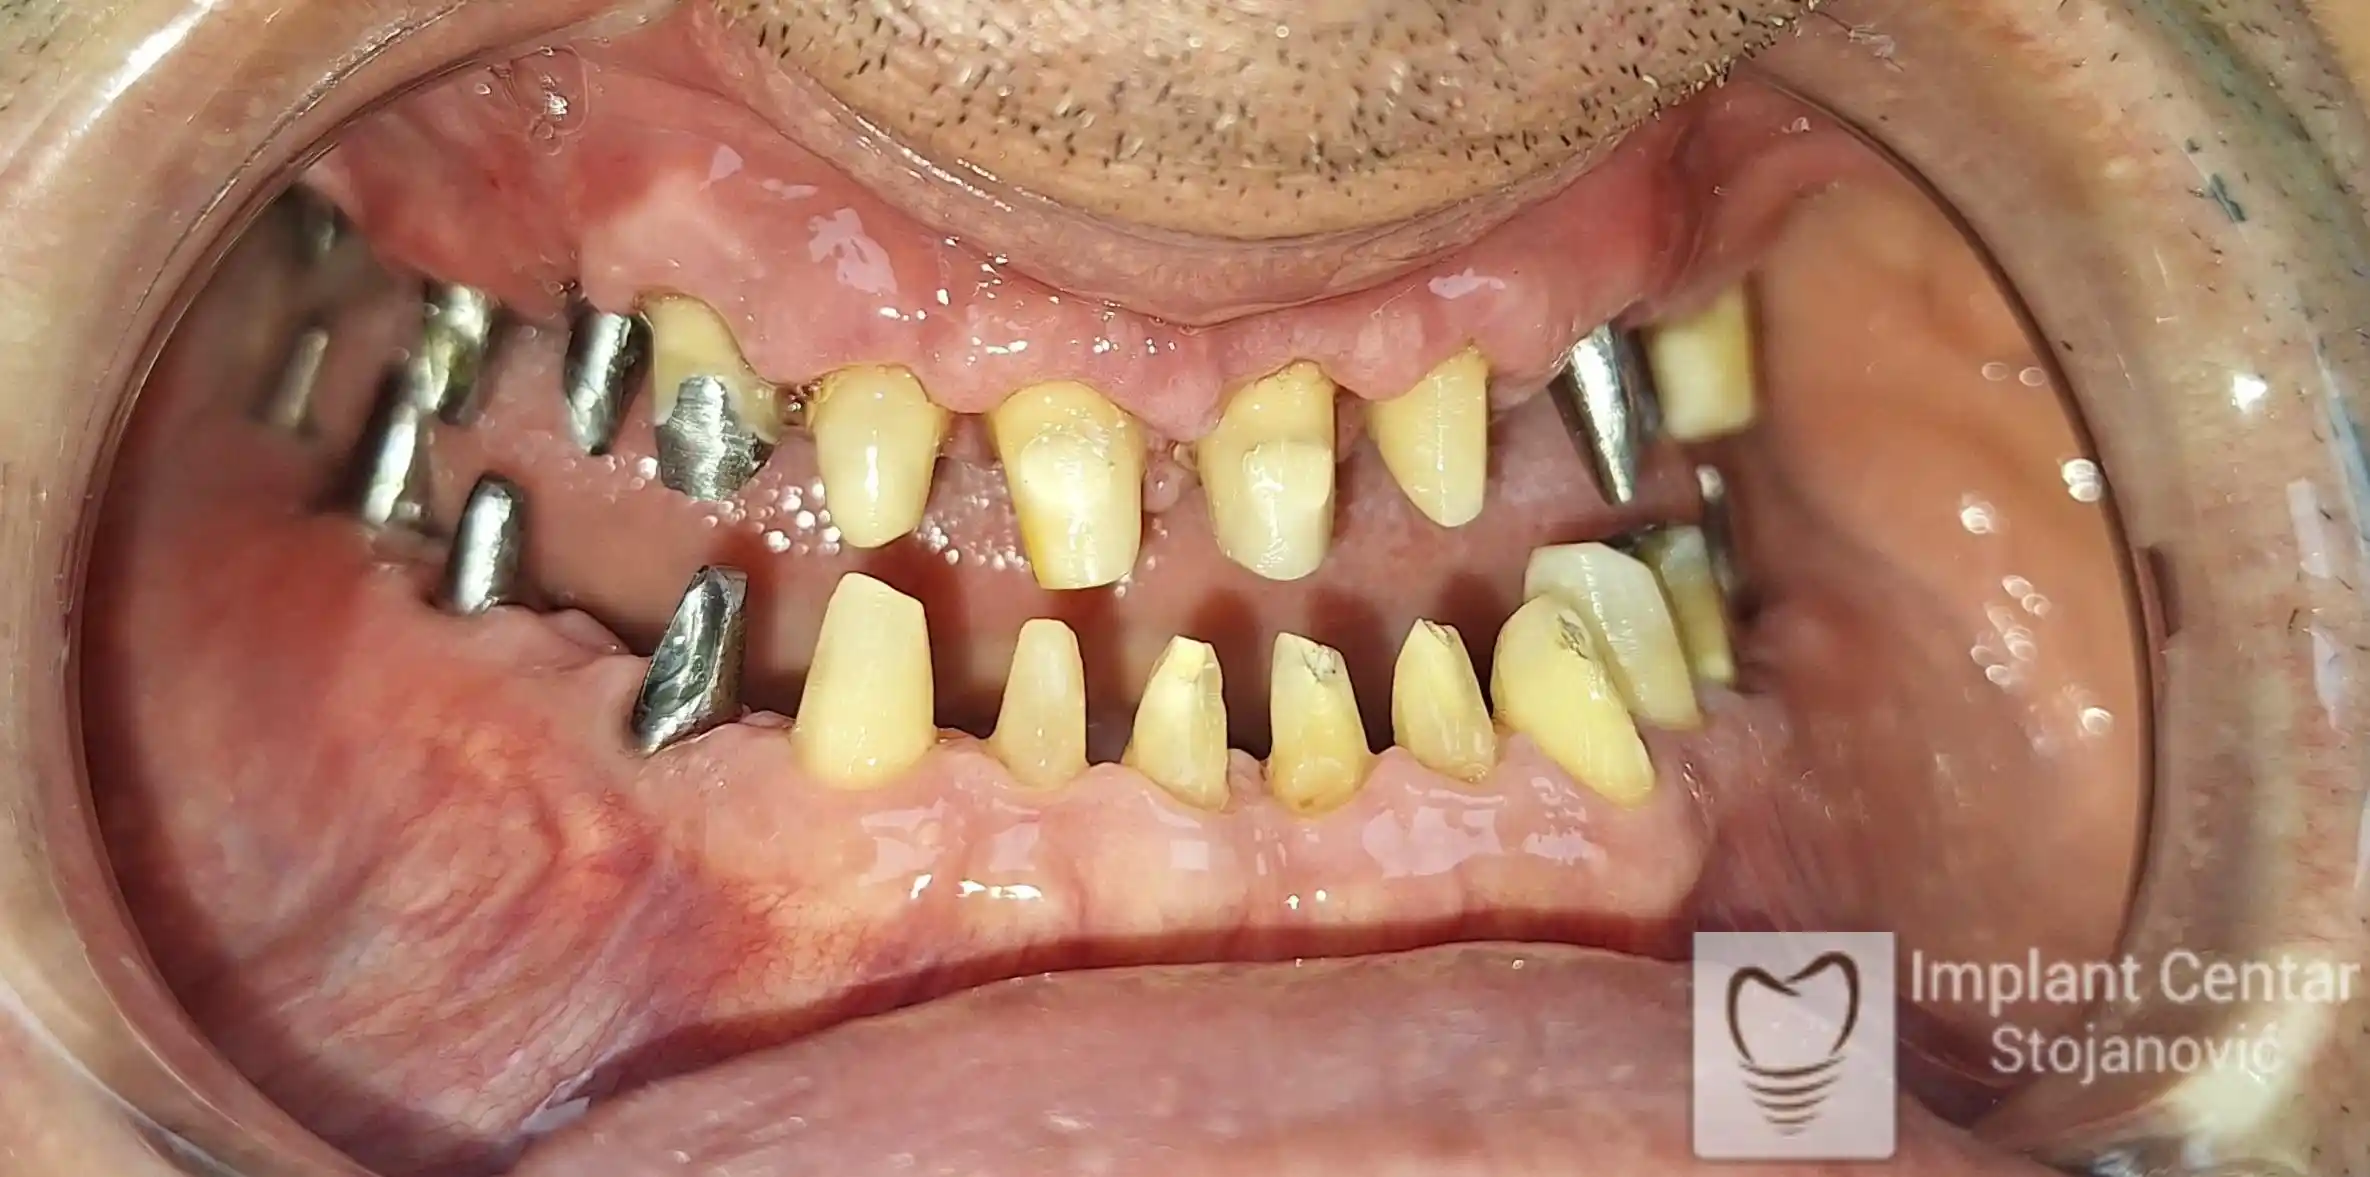

Na slikama 1 i 2 prikazan je klinički izgled pacijenta pre početka terapije. Nakon detaljnog kliničkog pregleda, analize radioloških snimaka, kao i razgovora sa pacijentom o njegovim željama i očekivanjima, izrađen je sveobuhvatan plan terapije. Terapija je podrazumevala vađenje preostalih zuba, ugradnju dentalnih implantata i izradu fiksnog protetskog rada na implantatima.

Tokom perioda osteointegracije, pacijent je bio zbrinut fiksnim privremenim krunicama na implantatima, čime su očuvani estetika i funkcija. Nakon završetka perioda integracije, izrađeni su definitivni cirkonijum-keramički mostovi (slika 6 i 7 ).

Pacijent je izuzetno zadovoljan postignutim rezultatom, jer su u potpunosti vraćeni prirodan izgled osmeha i puna oralna funkcija.